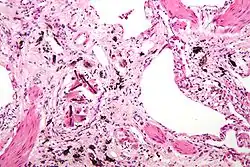

Micrograph of asbestosis (with ferruginous bodies), a type of pneumoconiosis. H&E stain.

• Asbestosisasbestos: Develops from inhaling asbestos fibers, leading to lung tissue scarring and reduced lung function. Symptoms include shortness of breath, persistent cough, and chest tightness.[12] Historically prevalent among workers in shipbuilding, construction, and manufacturing, especially those handling insulation materials containing asbestos.[13]